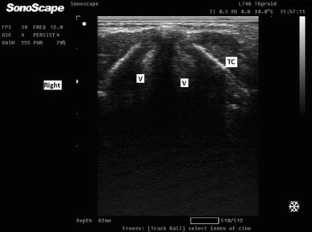

Fig. 3